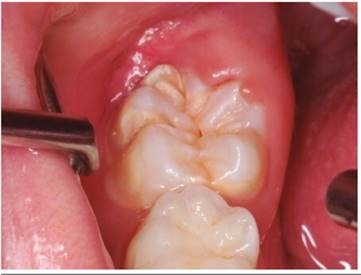

Paciente de género masculino de 07 años, 10 meses de edad, llegó a consulta con su mamá al Policlínico Dental de la Universidad Privada San Juan Bautista de Lima-Perú; refiriendo que el niño, presenta mucha sensibilidad, dolor al momento de ingerir sus alimentos y al realizar la higiene dental; le incomoda que el diente se vea de color amarillo-marrón. Al examen clínico extraoral (figura 01) no presenta ninguna alteración. Al evaluar el comportamiento (Escala de Frankl) el niño presentó comportamiento positivo. Al examen clínico intraoral (figura 02) el paciente presenta dentición mixta primera fase, erupción parcial de las primeras molares permanentes. varias piezas con fosas y fisuras profundas y también con HIM (B 3 II), la pieza 46 presenta fractura dental en superficie oclusal y vestibular, se observa 2/3 de erupción, que se diagnostica con HIM grado B 3 II (EAPO) debido a la distribución y forma de las manchas amarillo-marrón que presenta la pieza dental afectada. El pronóstico es reservado, a pesar de la colaboración del paciente y la persistencia de la mamá, ya que la pieza dental seguirá el curso de la enfermedad fracturándose, hasta que termine el proceso de erupción. No se requiere exámenes auxiliares. Se determinó realizar el tratamiento con Giómeros fluidos, para reconstruir la pieza, sellar fosas profundas y eliminar la sensibilidad en una sola sesión, por los beneficios antes mencionados.

Luego de considerar las medidas de bioseguridad se procedió con el tratamiento de la pieza 46 (Figura 1), se realiza aislamiento relativo por la falta de erupción total de la pieza y la excesiva sensibilidad del paciente, aplicó brix 3000 (gel enzimático para la remoción a traumática de tejido infectado) (brix SRL Argentina), sobre las superficies infectadas de la pieza 46, luego de 2 minutos, con una cureta de dentina (Mayleffer N° 46) eliminamos estructura dental con HIM (Figura 2), se lavó con agua, y secó, se realizó desproteinización de la cavidad dentaria con una bolita de algodón embebida con hipoclorito de sodio al 5% por 30 segundos, y se enjuagó con una bolita de algodón embebida en agua, secado con bolitas de algodón (Figura 3), luego de cambiar el aislamiento relativo; se aplicó el adhesivo de 7ma generación Palfique Bond (Tokuyama), por la sensibilidad del paciente, se airea, fotocura por 20 segundos (Figura 4), y se aplica Giómero fluido F00 de reconstrucción (Beautifil Flow Plus de Shofu inc.), dando forma con el bruñidor para resina cabeza de huevo y se fotocuró por 20 segundos (Figura 5). Se utilizó el Giómero fluido F03 de sellado de fosas y fisuras (Beautifil Flow Plus de Shofu inc.) fotocurando por 20 segundos (Figura 6). Finalmente se comprueba el ajuste oclusal con una fresa cilíndrica plana (108-009) eliminando excesos y porosidades (Figura 7a).